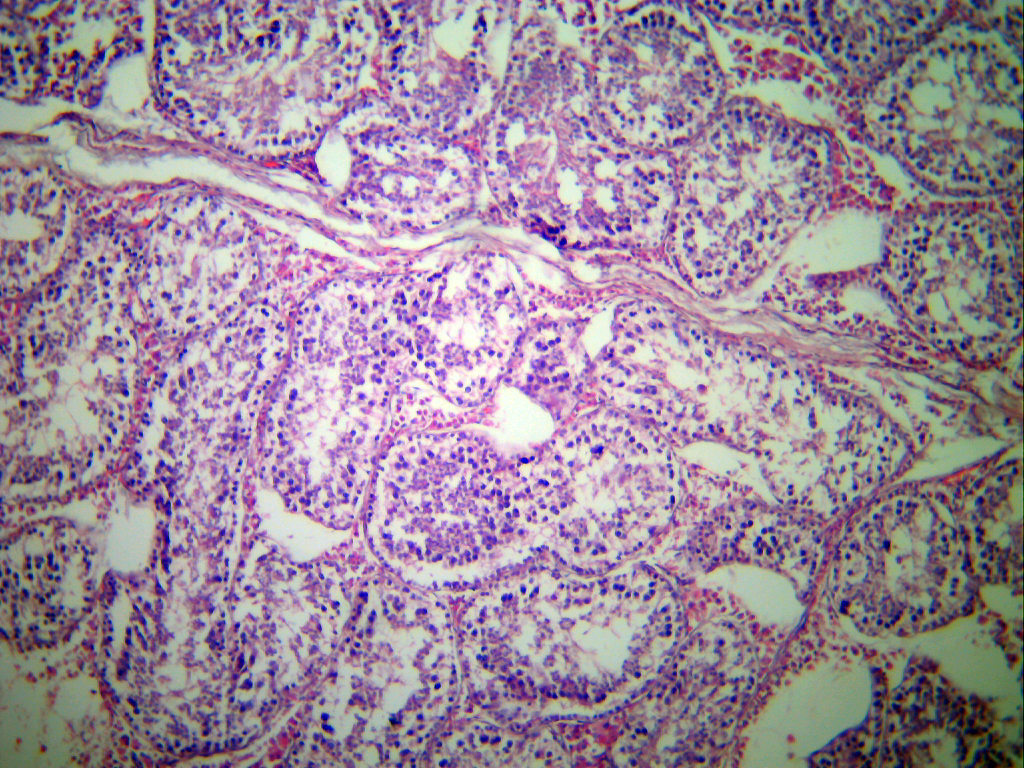

Testículo de cerdo (100 aumentos)

Fotografía de un testículo de cerdo.